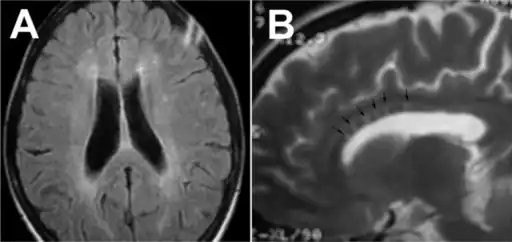

| Sagittal T1 image in a 19-year-old woman with Susac's syndrome showing the pathognomonic central callosal "holes" (microinfarcts) of SS. These residual "holes" (and sometimes, "spokes") develop as the acute callosal changes resolve. | |

In a recent analysis (Susac et al., 2003), MRI images from 27 patients fulfilling the diagnostic criteria of Susac's syndrome were reviewed. Multifocal supratentorial lesions were present in all patients. Most lesions were small (3 to 7 mm), though some were larger than 7 mm. All 27 patients had corpus callosum lesions. These all had a punched-out appearance on follow up MRI. Though most commonly involving white matter, many patients also had lesions in deep grey matter structures, as well as leptomeningeal enhancement. Multiple sclerosis (MS) and acute disseminated encephalomyelitis (ADEM) can mimic the MRI changes seen in patients with Susac's syndrome. However, the callosal lesions in Susac's syndrome are centrally located. In comparison, patients with MS and ADEM typically have lesions involving the undersurface of the corpus callosum. Deep gray matter involvement commonly occurs in ADEM but is very rare in MS. Leptomeningeal involvement is not typical of either MS or ADEM. What this means is that if 10 lesions are found in the brain of an MS patient, a lesion may be found in the corpus callosum. If you have 10 lesions in a Susac patient, more than half will be in the corpus callosum.